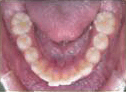

- 矯正治療開始前,

- 要進行一些簡單的常規檢查與記錄,了解口腔與牙齒的情況:

- a. 口內及顏面外觀照相記錄。